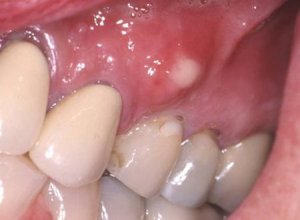

Абсцесс зуба — это инфекционное воспаление, вызванное бактериями, которое ограничено здоровыми тканями и сопровождается образованием гноя.

Это заболевание может затрагивать корень зуба, десны и соседние ткани.

- Отечность и покраснение десен (в результате воспалительного процесса);